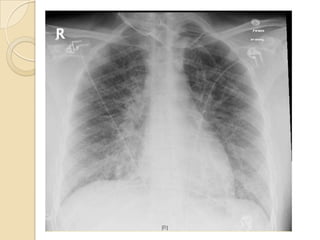

 At the Start, Subtle reticular or ground

glass opacities, often with Kerley B

lines

 Small pleural effusions are common

Imaging  At theStart, Subtle reticular or ground glass opacities, often with Kerley B lines  Small pleural effusions are common